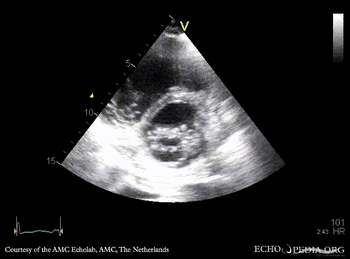

E00450.gif E00451.gif

PLAX: prolaps of PMVL, huge amount of pleural effusion PLAX: Color Doppler, severe mitral regurgitation, excentric jet